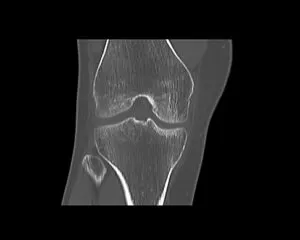

CT

GE社製Revolution ACT(16列)を導入しています。X線を利用して体の断面(輪切り)を撮像する検査です。この輪切りの画像をコンピューターで処理することにより、様々な方向からの断面像や3D画像を得ることができます。

CTで検査した画像